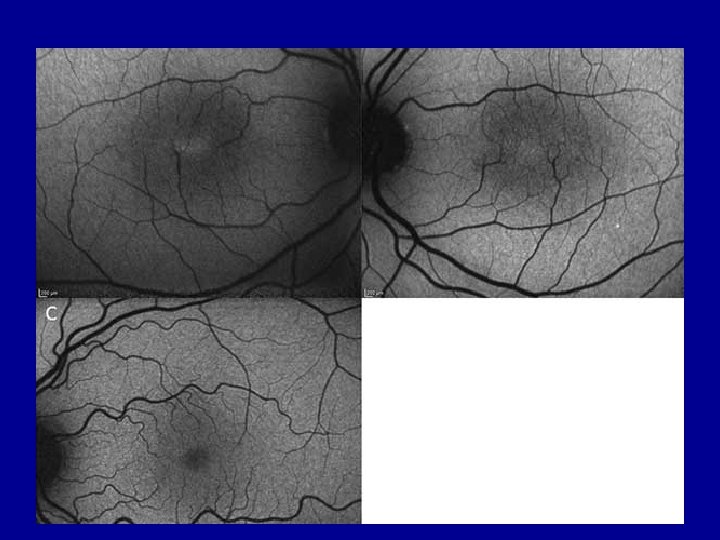

MACTEL • Not an ‘AMD’ • Important as does not respond to anti VEGF